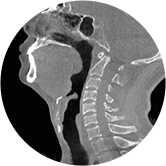

頸椎

腰椎

精準診斷

手術方案規劃

術后隨訪